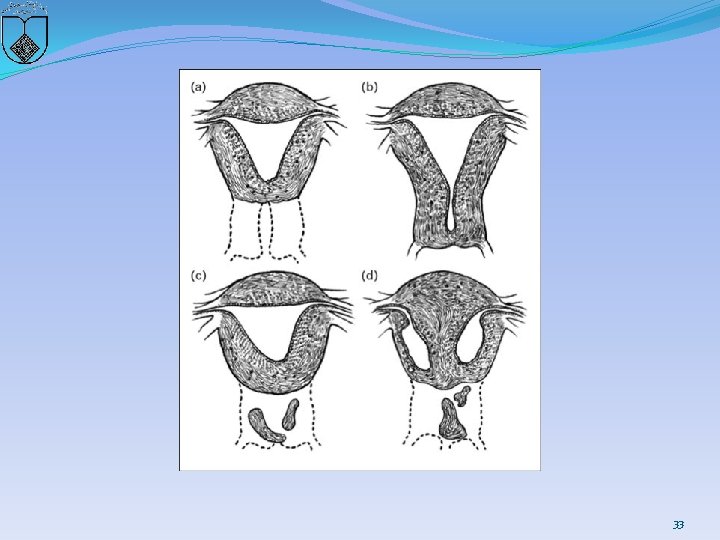

Two basic categories of cervical anomalies �first type: � cervical aplasia, lack a uterine cervix �lower uterine segment narrows: terminate in a peritoneal sleeve at a point well above the normal communication with the vaginal apex 30

31

�second type, cervical dysgenesis (1) Cervical body consisting of a fibrous band of variable �length and diameter (endocervical glands may be �noted on pathologic examination; (2) Intact cervical body with obstruction of the cervical �os (cervical ostium; the cervix is usually well formed, �but a portion of the endocervical lumen is obliterated; (3) Stricture of the midportion of the cervix (which is �hypoplastic with a bulbous tip and no identifiable �cervical lumen; (4) Fragmentation of the cervix (with portions that can �be palpated below the fundus and that are not connected �to the lower uterine segment 32